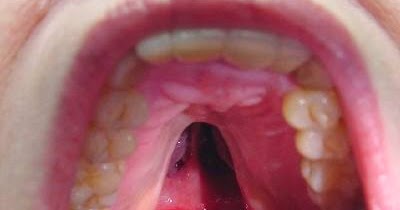

علاج التهاب سقف الحلق بالاعشاب ، يعتبر الحلق من أهم أجزاء الفم فهو الذي يفصل بين التجويف الأنفي والفمي، وله وظيفة مهمة وهي الاحساس بطعم ونكهات الطعام، وقد يصاب سقف الحلق بالالتهابات التي تؤثر على مهمته ووظيفته مما يشعر المريض بالألم وعدم الراحة.

اعراض التهاب سقف الحلق

1- الاحساس بالألم عند تناول الطعام أو الشراب أو عند البلع.

2- الإحساب بعدم الراحة والألم عند تناول الطعام الساخن.

3- الشعور بالوخز في منطقة سقف الحلق.

4- ظهور التقرحات المؤلمة والمزعجة.